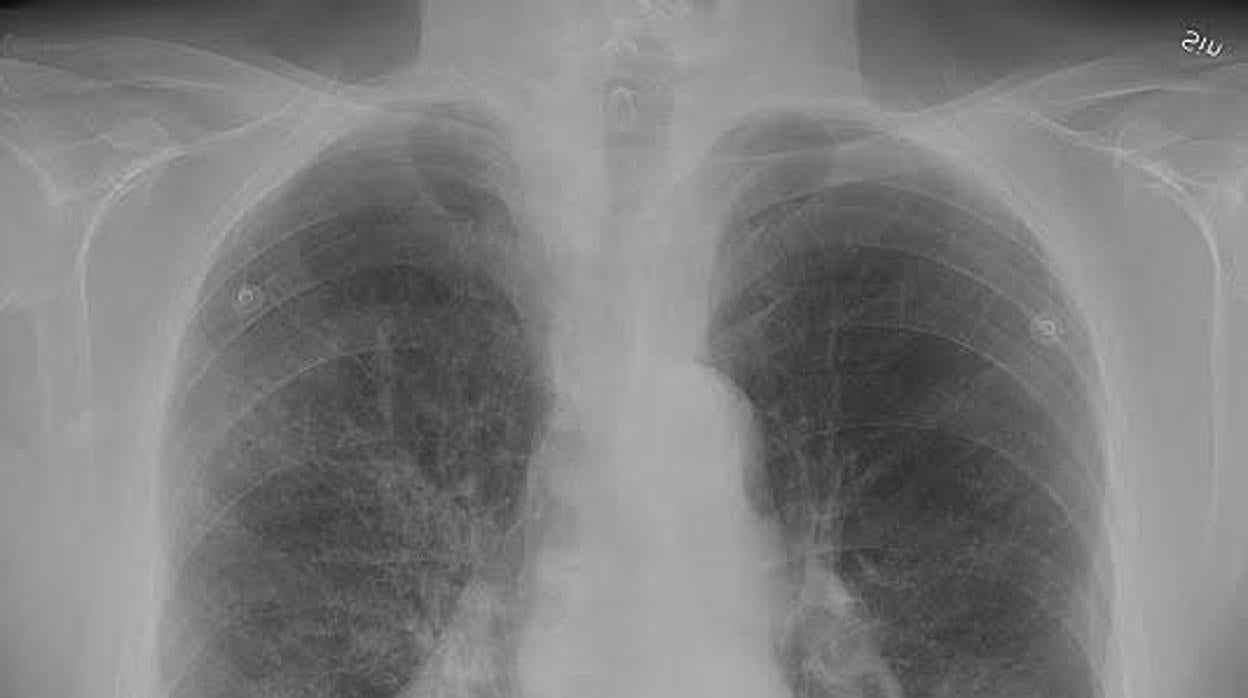

La EPOC ya constituye la cuarta cuarta causa de muerte en nuestro país WIKIPEDIA

La enfermedad pulmonar obstructiva crónica (EPOC) es un trastorno pulmonar caracterizado por una obstrucción progresiva, y por lo general irreversible, de las vías respiratorias. Una enfermedad que, ligada directamente al consumo de tabaco, padecen más de 2,9 millones de españoles –y hasta 174 millones de personas en todo el mundo– y que supone ya la cuarta causa de mortalidad en nuestro país. De hecho, la EPOC fue responsable de 29.000 decesos en España solo en 2015. De ahí la importancia, vital, de detectar esta enfermedad –lo que en nuestro país solo sucede en un 27% de los casos– y administrar los tratamientos necesarios para frenar su progresión. Pero, ¿hay alguna manera de saber si la EPOC podría evolucionar de forma agresiva, llegando incluso a causar el deceso del paciente? Un aspecto muy importante dado que identificaría a la población en riesgo de sufrir un empeoramiento significativo de la enfermedad y, por tanto, posibilitaría la toma de medidas para tratar de minimizarlo, caso de la toma de tratamientos más intensivos. Y según un estudio dirigido por investigadores de la Universidad de la Columbia Británica en Vancouver (Canadá), la respuesta es sí: tan solo hay que evaluar la longitud de los telómeros de las células sanguíneas.